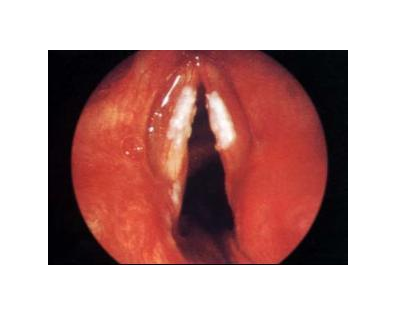

慢性肥厚性喉炎

表现为声带粘膜慢性充血肥厚(增厚),开始平坦光滑,渐渐变得增厚、粗糙,较后癌变。